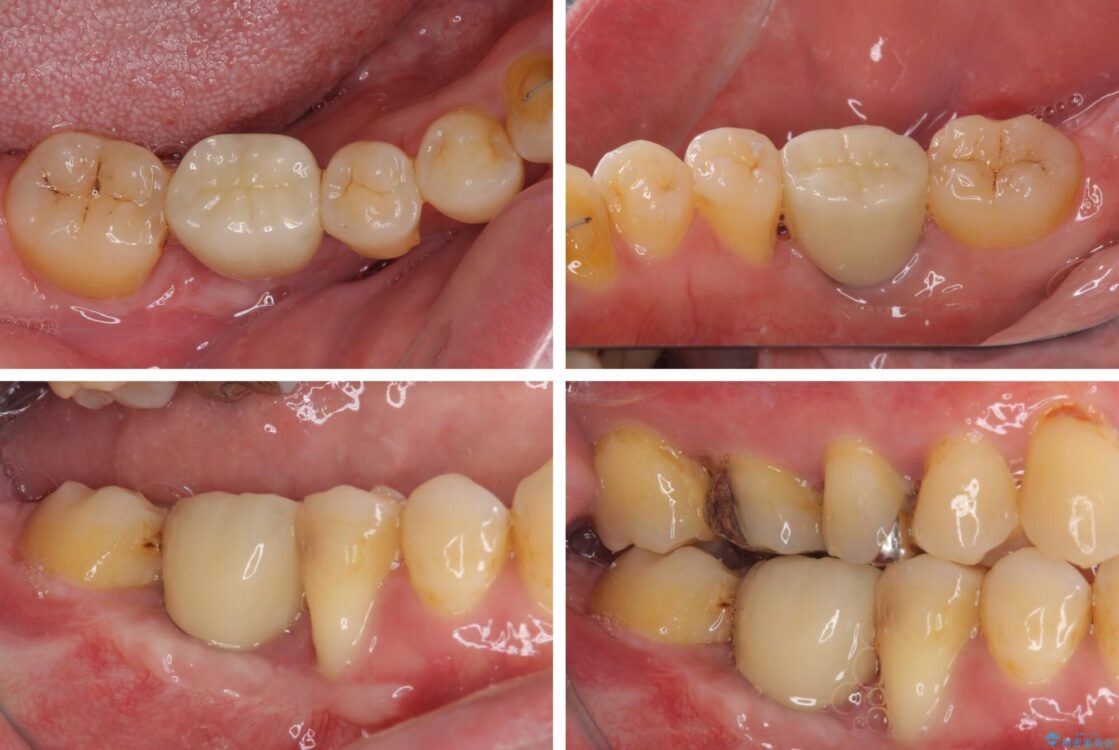

奥歯の痛みと前歯のデコボコを気にして来院された患者様です。

左右下顎の大臼歯は、ともに歯根が破折しており、抜歯が必要な状態でした。

放置したことで炎症による骨吸収が顕著であるため、骨造成を併用してインプラント埋入を行うこととしました。

咬み合わせは受け口傾向であり、上顎前歯の叢生が顕著であったことから、第1小臼歯抜歯による矯正治療も検討しましたが、下顎大臼歯を左右ともに抜歯するため、非抜歯による矯正治療を行うこととしました。

治療前